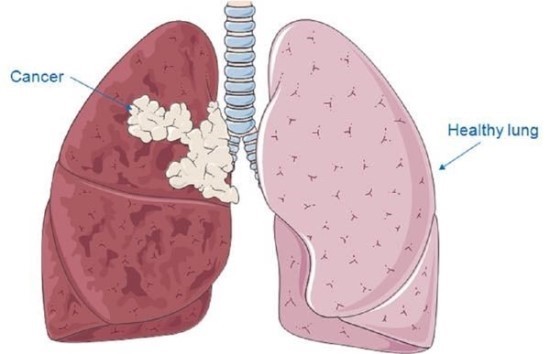

안녕하세요! 오늘은 폐렴의 초기 증상에 대해 알아보려고 합니다. 갑자기 기침이 심해지거나 숨이 차는 등 평소와 다른 호흡의 변화가 있을 때, 그 증상이 단순한 감기인지 아니면 폐렴으로 이어지는 문제인지를 구분하는 것이 중요합니다. 폐렴은 빠르게 진행될 수 있기 때문에, 초기 증상에 대한 인식을 높이는 것이 예방과 치료에 큰 도움이 됩니다.

폐렴 초기증상 폐렴 초기증상